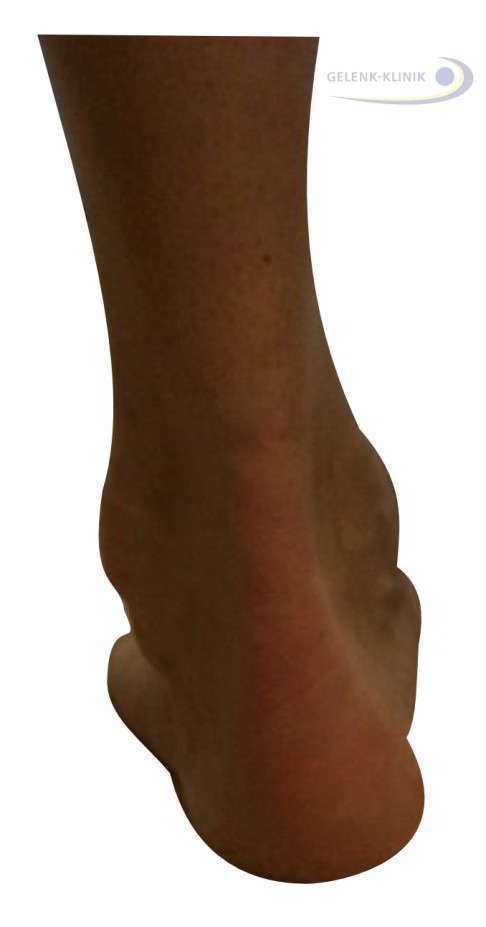

Varusstellung des Rückfußes: Das Fersenbein kippt nach innen

Die Verkippung des Fersenbeins nach innen führt zu einer Überlastung. Häufig schädigt dies auch die Außenbänder: Weil sich die Beinachse nach außen verlagert, müssen die Außenbänder viel mehr Last tragen.

Zudem kann diese Steilstellung der Ferse zu Reizungen der Weichteile führen. Hier können Schleimbeutelentzündungen im Bereich des Achillessehnenansatzes entstehen. Überbeine (Exostosen) an der Ferse, auch Haglundexostosen genannt, können daraus resultieren. Durch die Fehlstellung des Rückfußes beim Hohlfuß entstehen an der Ferse besonders häufig chronische Schmerzen.

- Varusfehlstellung (O-Fehlstellung) des Fersenbeins